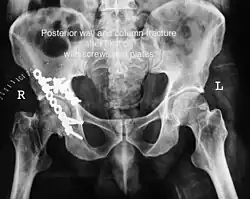

The final management depends on the size of the fragment(s), stability and congruence of the joint. In some cases traction for six to eight weeks may be the only treatment required; however, surgical fixation using screw(s) and plate(s) may be required if the injury is more complex. The latter treatment will be called for if bone fragments do not fall into place, or if they are found in the joint, or if the joint itself is unstable.

Innominate bone is a flat bone with many curves. In most part the bone is thick enough and has broad surfaces that are amenable to primary fixation using lag screw(s) and to neutralize forces across the bone one needs to add plate(s) on the surface of the fractured fragments for it to heal without deformity.

Implants : normally lag screws and reconstruction plates are preferred implants